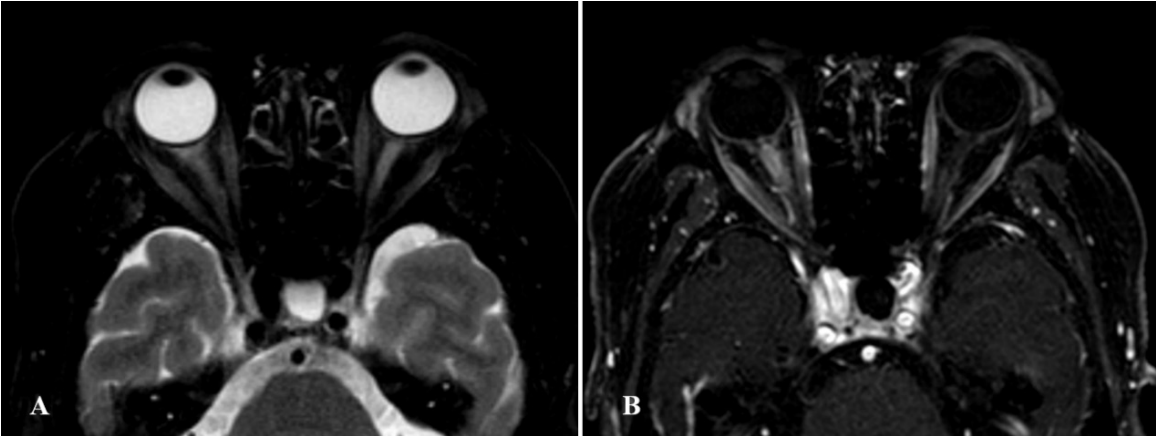

20230403094940_2900.png

图 6 眼眶增强 MRI

Figure 6 Enhanced MRI of the orbit

右侧视神经增粗,眶内段及管内段可见长 T2 信号,T1 可见不均匀强化,左眼视神经较对侧稍细小,T1 强化较对侧稍减低 .

It showed that the right optic nerve was thickened, with long T2 signal and uneven T1 reinforcement in the intraorbital and tubular segments, and the left optic nerve was slightly smaller than the contralateral one, and the T1 reinforcement was slightly reduced compared with the contralateral one.